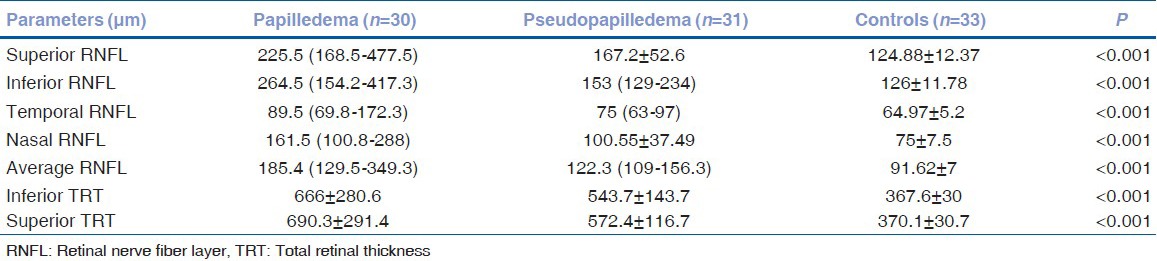

Figure 1.

The triangular subretinal hyporeflective space in papilledema (a, b) and the buried optic nerve head drusen in pseudopapilledema (c, d)

Use of optical coherence tomography in diagnosing papilledema

Initial studies using the TD-OCT looked at the RNFL thickness in mild papilledema and pseudopapilledema and the results as to the difference between the thickness in both the groups were variable with Karam and Hedges reporting no statistically significant difference between the two groups and Johnson et al. stating that the differences in mean RNFL thickness between papilledema and ONHD were significant.[4,14] Johnson et al. also described a qualitative criteria for differentiating papilledema and pseudopapilledema using stratus OCT, he described the disc appearance on the OCT of papilledema as an elevated optic nerve head with smooth internal contour and subretinal hyporeflective space (SHYPS) with recumbent “lazy V” pattern whereas ONHD displayed a “lumpy-bumpy” internal optic nerve contour and a rapid decline in SHYPS thickness.[4] In our study also, the SHYPS was noted in papilledema (as mentioned previously) and in pseudopapilledema. Fig. 1 describes the difference between the shapes of this hyporeflective space in the two conditions: (a) The triangular space is larger in papilledema and appears smaller in pseudopapilledema, (b) the wider part of the triangle abuts the buried drusen which appears as a discrete hyperreflective echo just as described by Lee et al.[5] Another study by Wester et al. with stratus OCT studied the OCT differences between the ONHD, papilledema and small crowded discs.[15] They described ONHD as typically elevated disc surface on the OCT and appeared as an optically empty cavity, sometimes with a perceptible reflection from the posterior surface whereas in papilledema, there was strong anterior reflection due to which to structures were seen behind it. In congenitally crowded disc there is a minimal anterior reflection with slight elevation of the optic disc. More recent studies with SD-OCT have been able to look at the morphology of the ONHD and a congenitally anomalous disc in more detail. Lee et al. have described ONHD as a focal, hyperreflective, subretinal mass with a discrete margin on SD-OCT.[5] This study states that the retinal nerve fiber thickness in the nasal section provides a good differential marker for optic disc edema from ONHD. In our study of the 20 eyes of 11 patients with a doubtful diagnosis of pseudopapilledema, 19 eyes of 10 patients revealed a hyperreflective mass under the peripapillary retina especially in the nasal retina [Fig. 2] just as described by Lee et al.[5] In one patient, the pseudopapilledema was secondary to vitreopapillary traction which can be easily identified on the SD-OCT as described by Houle and Miller[16] Hence, in all (100%) patients with pseudopapilledema with a buried drusen, the ONHD was seen on OCT. Flores-Rodríguez et al. in their recent paper have suggested that there is no significant difference between TD-OCT and SD-OCT in diagnosing a pseudopapilledema and that the new quantitative parameters of papillary elevation and RNFL measurements showed greater sensitivity and specificity than the qualitative criteria which probably are seen better on the SD-OCT. Karam and Hedges argued that the study group in all the studies in favor of using OCT as a tool to differentiate between disc edema and pseudopapilledema had subjects with variable causes of disc swelling in the group with disc edema and could not be used to represent papilledema.[14,17] We found that in children, the ONHD is associated with normal RNFL thickness and as the age advances the RNFL thickness profile changes probably secondary to the progressive displacement of the fibers by the buried drusen.